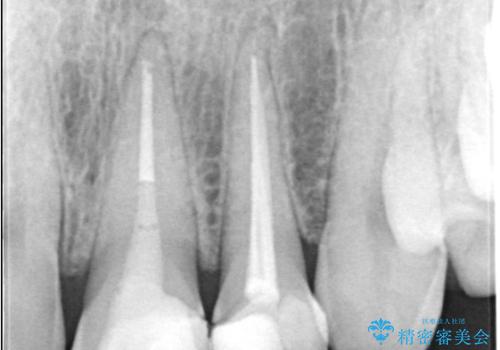

治療はまず、審美性を最大限に高めるために、歯肉のラインや前歯の形を整えることから始めました。その後、4本の歯を丁寧に形成し、金属を一切使用しないオールセラミッククラウンを作製しました。

オールセラミックは、光の透過性が天然歯に非常に近いため、周囲の歯と見分けがつかないほどの透明感と自然な色調を再現できます。また、プラークが付着しにくく、金属アレルギーの心配もありません。